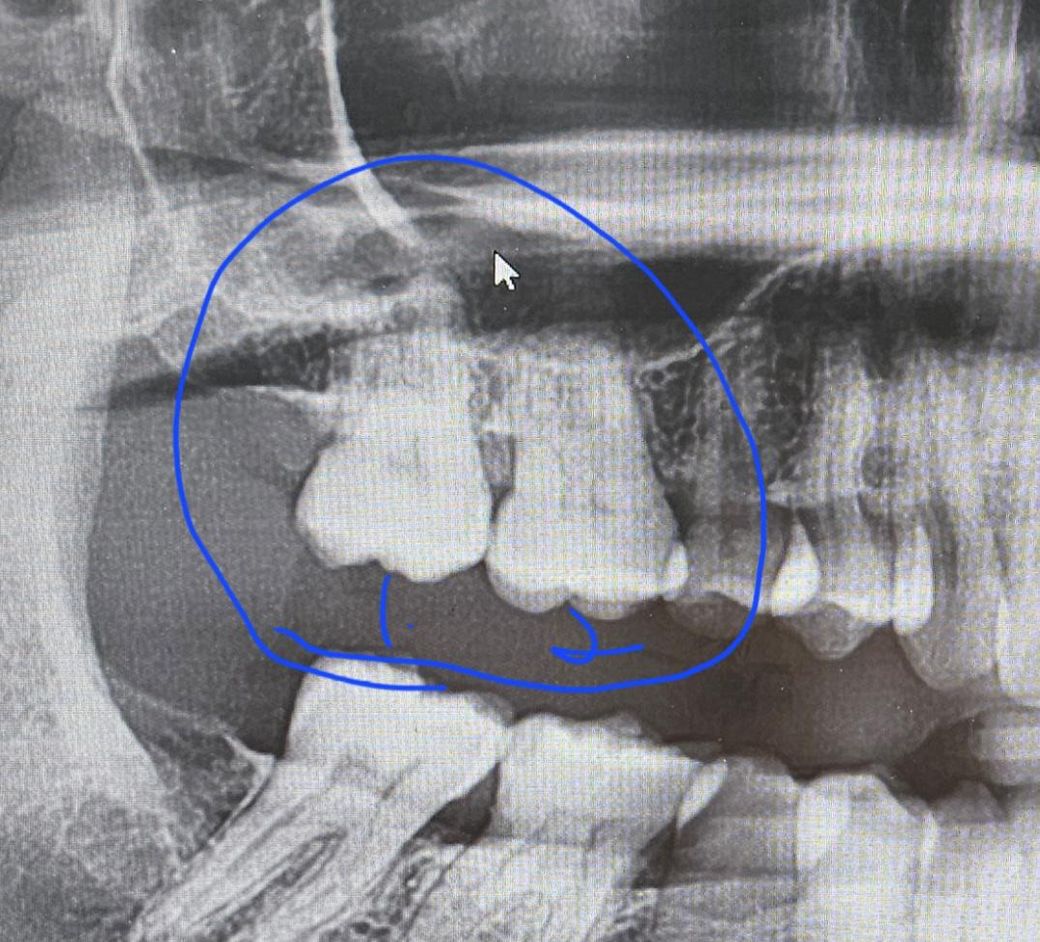

엑스레이와 사진찍어 보여 주시면서 사진상 1번과 2번이 만나는 부분에 충치가 있다고 하셨습니다.

• 2번 째 사진

사진으로 봤을 경우에 인접면에 충치가 보이기는 하지만 방사선 사진상에는 큰 충치가 보이지 않습니다. 따라서 많이 진행이 되지는 않은것으로 보입니다.

네 육안사진상 인접면 충치 있어보입니다 엑스레이는 파노라마 보다는 치근단을 치아끼리 겹치지 않게 찍어봐야합니다